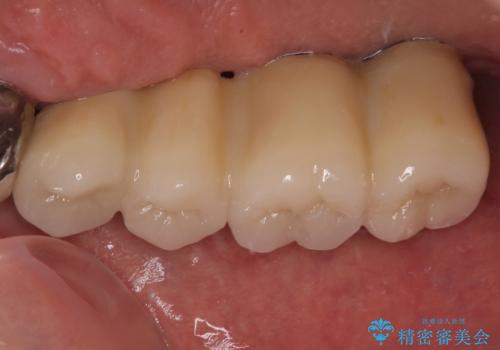

インプラントが無事に生着した後に、オールセラミッククラウンにて補綴治療を行うこととしました。

後方2本を先に埋入し、即日で仮歯を装着しましたが、徐々にインプラントが骨内で緩んでしまい、手前のインプラント埋入時に再埋入することとなりました。

再埋入後は緩くなることもなく、無事に補綴治療を行うことができました。